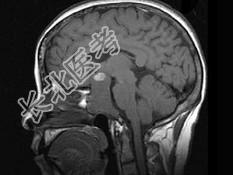

- 单项选择题女,55岁, 1年前出现头痛,头昏, 症状间断性加重,半年后出现视物模糊, 且视力逐步下降,以右侧为甚, 根据所提供图像,最可能的诊断是 ( )

B、颅咽管瘤

C、垂体腺瘤

D、脑膜瘤